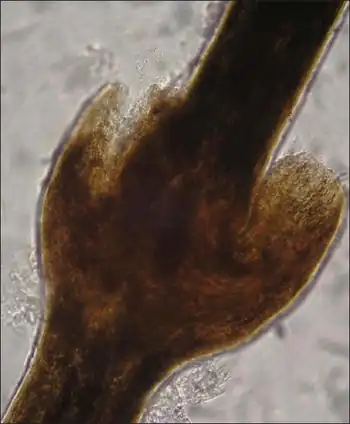

| Light microscopic examination of scalp hair shows typical trichorrhexis invaginata | |

Trichorrhexis invaginata, or bamboo hair, is a hair shaft abnormality that occurs as a result of an intermittent keratinizing defect of the hair cortex. Incomplete conversion of the sulfhydryl –SH group onto S-S disulfide bonds in the protein of the cortical fibers leads to cortical softness and subsequent invagination of the fully keratinized distal hair shaft into the softer, abnormally keratinized proximal hair shaft. Intussusception of the distal hair shaft into the proximal hair shaft results in a distinctive ball-and-socket hair shaft deformity. The affected hairs are brittle and breakage is common, resulting in short hairs.[6]